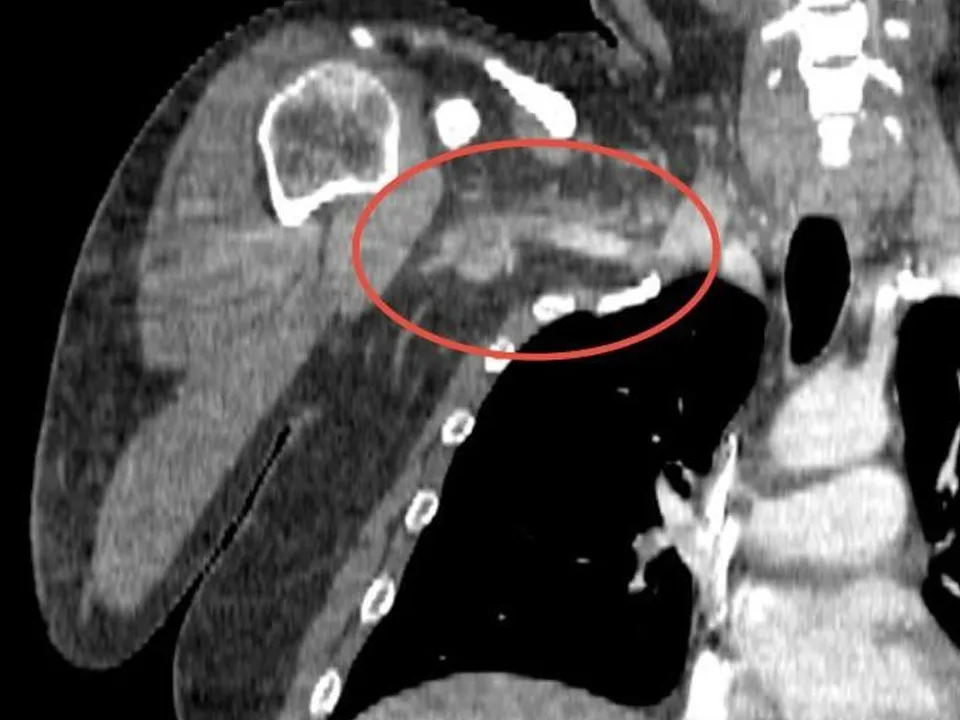

Врачи Центра спасения конечностей Долгопрудненской больницы провели операцию по извлечению тромба 34-летнего пациента. Мужчина поступил в больницу с жалобами на онемение правой руки, боли в области плеча и шеи, «вспышки» перед глазами, слабость и головокружение. Согласно данным, симптомы проявлялись несколько часов и быстро прогрессировали, вынуждая пациента обратиться за медицинской помощью.

Обследование показало отсутствие кровотока в подмышечной, подключичной и плечевой артериях с правой стороны.

Операция длилась полтора часа. Врачи использовали специальный баллон, чтобы аккуратно удалить тромб. Баллон, раскрывшись внутри сосуда, продвигал сгусток к месту разреза в районе локтя, откуда тромб был извлечен с помощью хирургического инструмента. Пациент мог лишиться конечности, если бы тромб остался без лечения, а отрыв тромба и попадание его в мозг угрожали бы смертельным исходом.